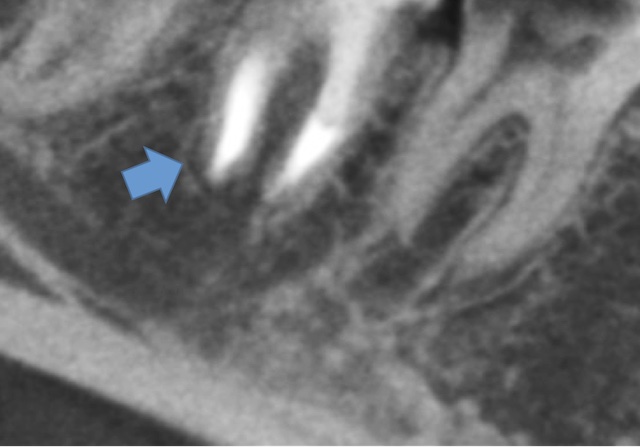

かぶせ物が不適であること(青矢印部)、近心根に根尖病巣があること(青枠部)、根充剤がかなり太いため(赤矢印部)歯質が薄くなっていることなど問題点がいくつかありましたが、他院で治療をしたばかりであり、また上記の条件から再治療には抜歯のリスクが非常に高いことから初診時は患者さんと相談し経過観察することになりました。